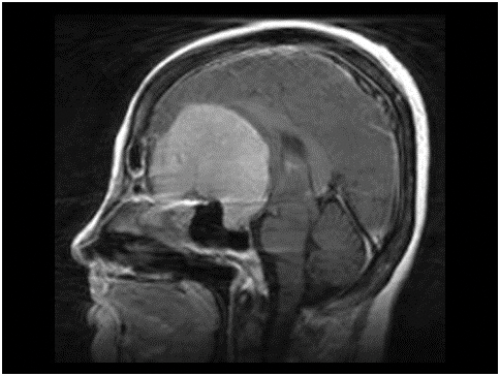

Figure 6: MRI of brain showing huge olfactory groove meningioma.

In the early stages of papilloedema visual function is normal unless, as in the case of some brain tumours, which compress the optic nerve or visual pathway, there will be loss of visual acuity or of the visual fields. If papilloedema progresses untreated the disc swelling will gradually subside and the nerve axons will die, functional loss first developing with constriction of the peripheral fields and progressing to tubular fields (Figure 5). Optic atrophy (Figure 6) will also develop as the nerve axons die leading to blindness. Thus it is essential that the cause, be it a tumour, infection, pseudo tumour cerebri / idiopathic intracranial hypertension (PTC / IIH) etc. causing raised intracranial pressure, be treated before these latter complications develop. In all cases of papilloedema regular evaluation of the peripheral visual field preferably by Goldmann or similar perimeter is essential both pre and post operation in the case of a brain tumour, and in other causes of raised ICP with papilloedema, such as PTC / IIH, regular supervision with appropriate perimetry is also required.

The name of this rare syndrome is well known to ophthalmologists but they may not be aware of its origin or true nature. It was described in 1911 [2] by Robert Foster Kennedy (1884-1952), who was born in Belfast and became Professor of Neurology at Cornell University, New York, but the condition had been noted as early as 1893 by Sir William Gowers, another famous British Neurologist. The syndrome consists of ipsilateral optic atrophy and contralateral optic disc oedema resulting from a brain tumour in the frontal lobe of the brain, usually an olfactory groove meningioma (Figure 6). Such a lesion must first compress its adjacent optic nerve and later cause raised ICP because the axons in an already atrophic ON cannot develop axoplasmic flow stasis, swell, compress the blood vessels and produce disc oedema.